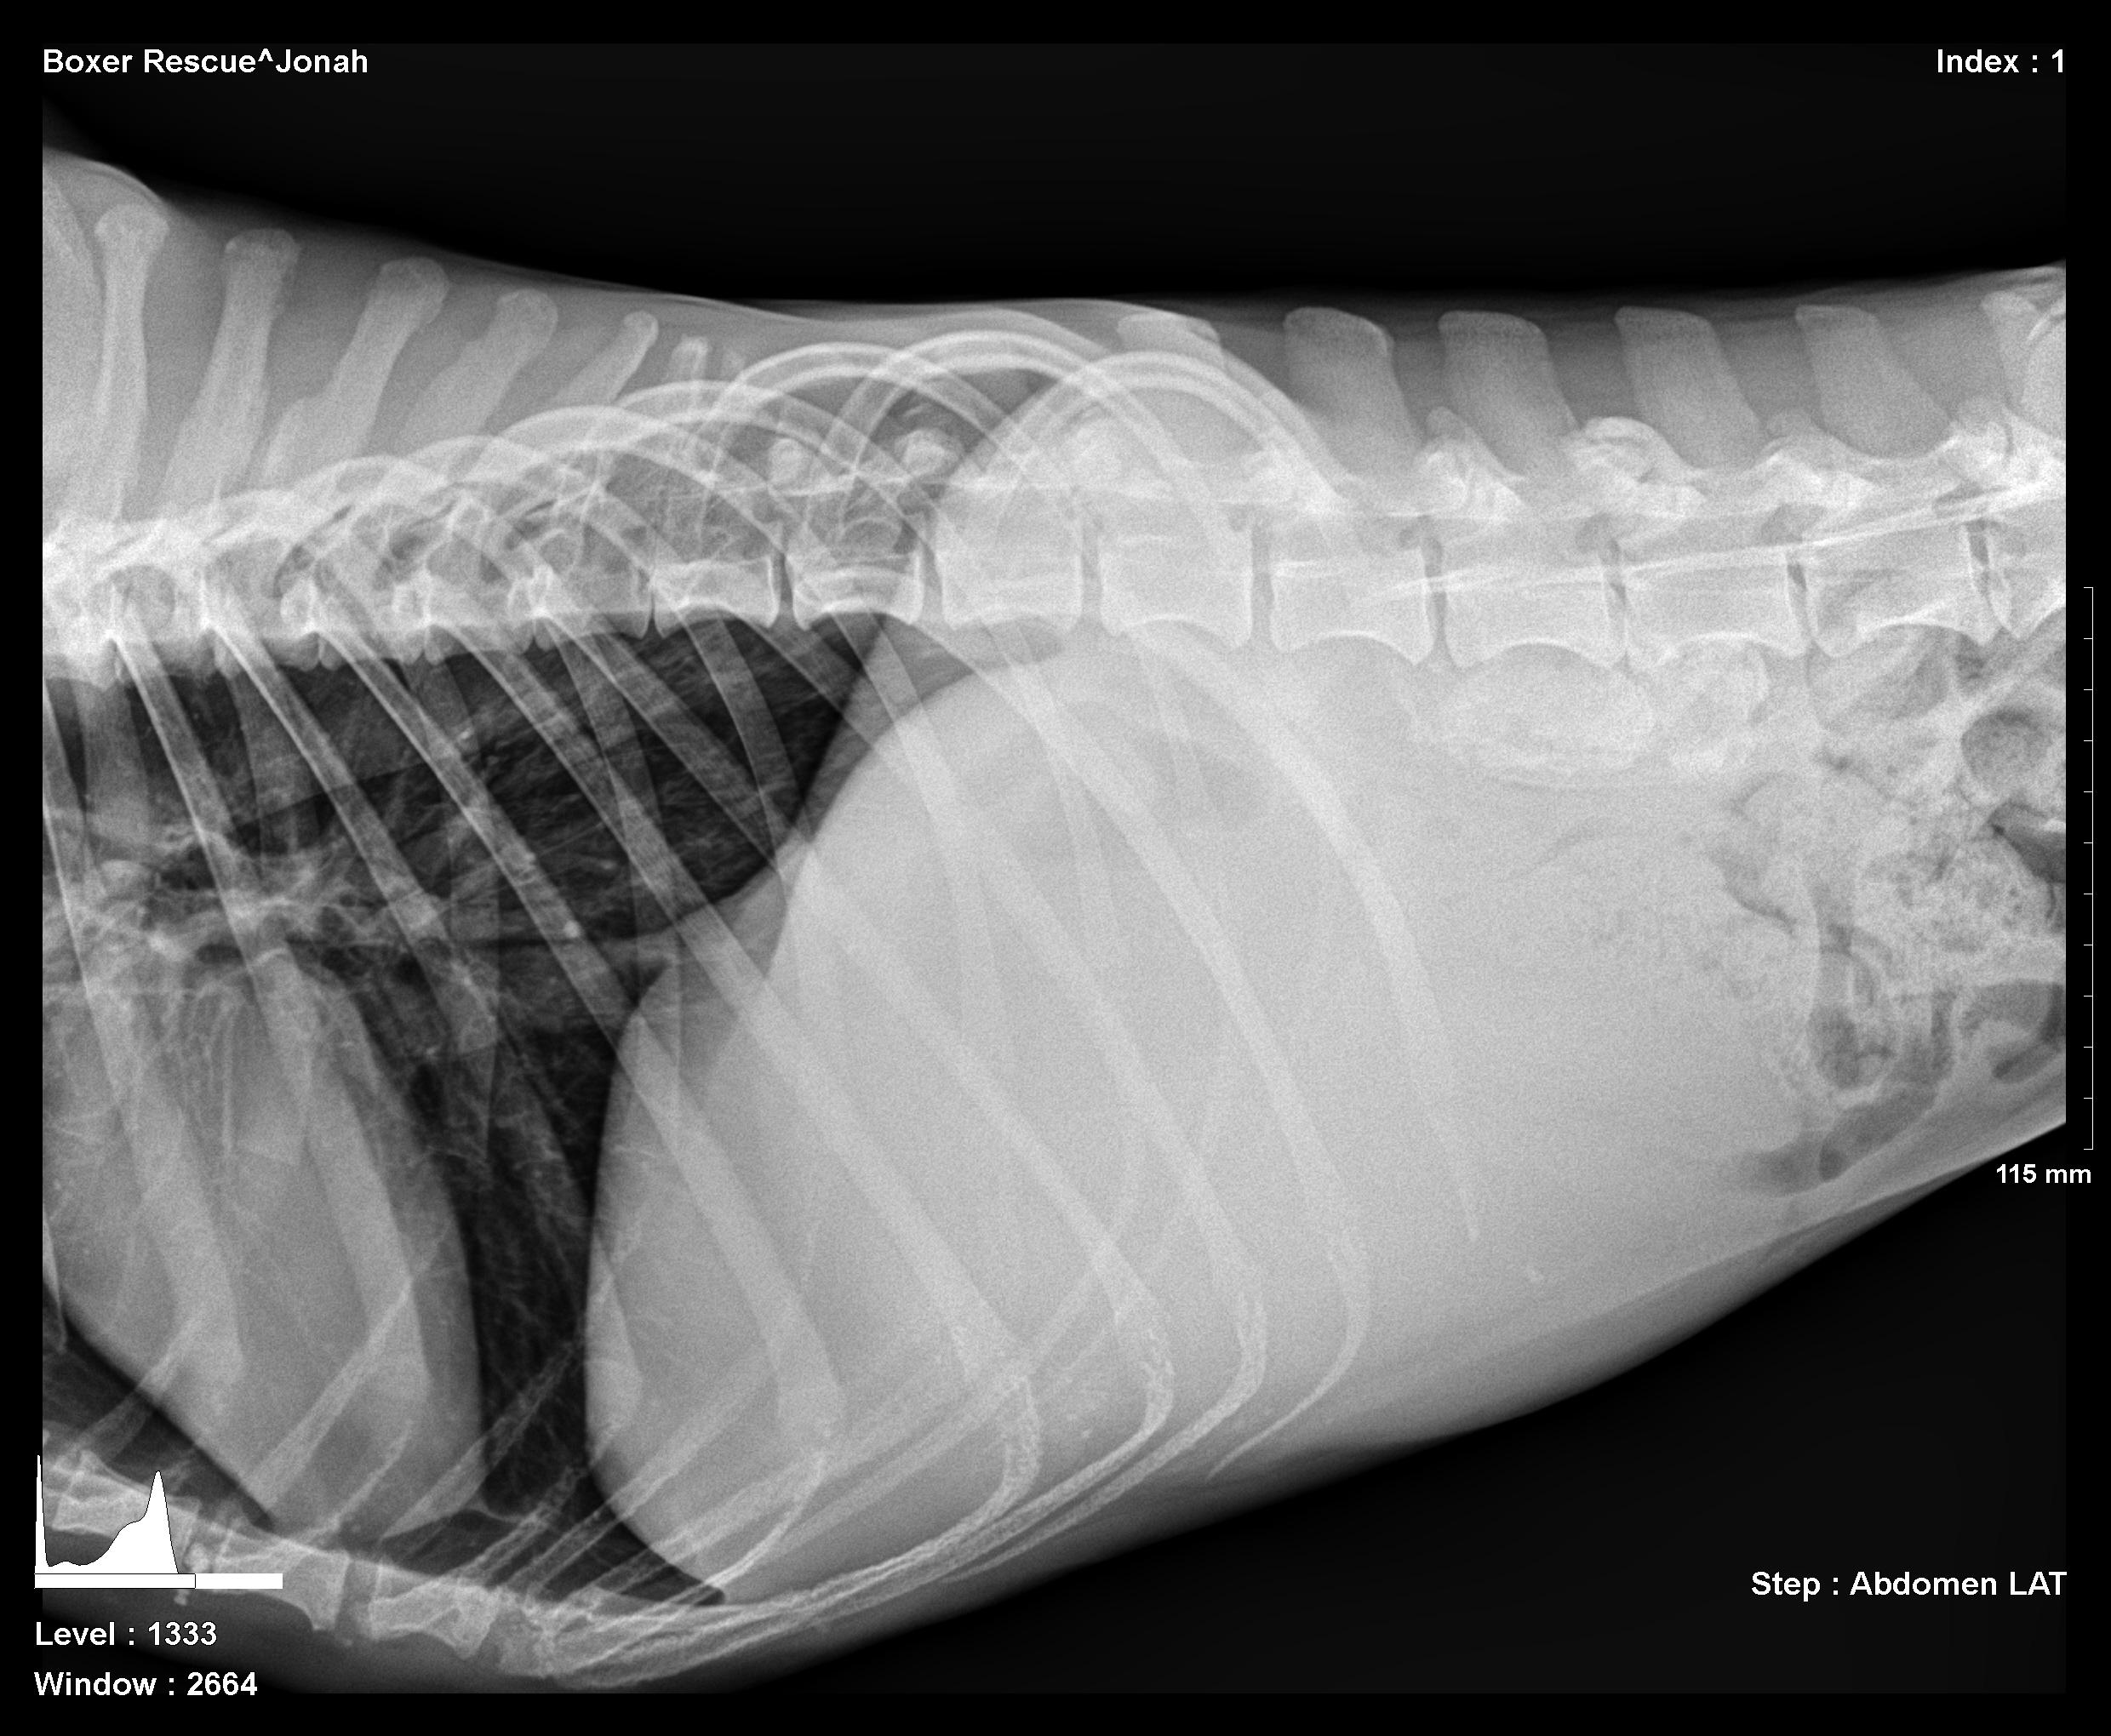

The patient is a 5 year old neutered male Boxer. The dog was presented to the clinic by a rescue organization. He was emaciated, vomiting, and anorexic. Bloodwork was unremarkable. Physical exam revealed a mid abdominal thickening potentially of intestinal origin. Lateral radiograph revealed a mid-cranial abdominal mass with mass effect upon the intestinal tract displacing the mesentery caudally. A volume-contracted heart was also visible (Image 1).